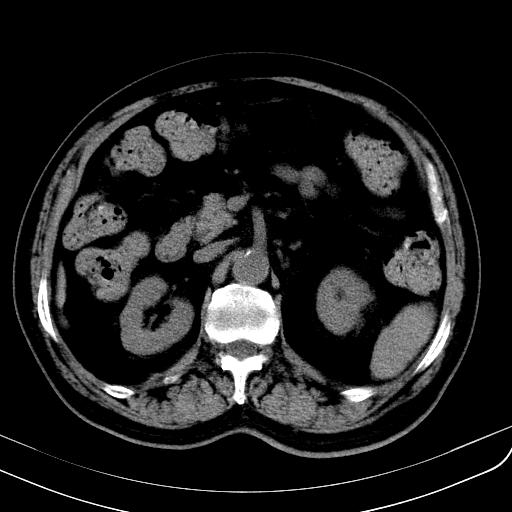

胃底靠近胃大弯处可见一圆形软组织影,直径为3.45cm,ct值约为30.1hu

请会诊!!!